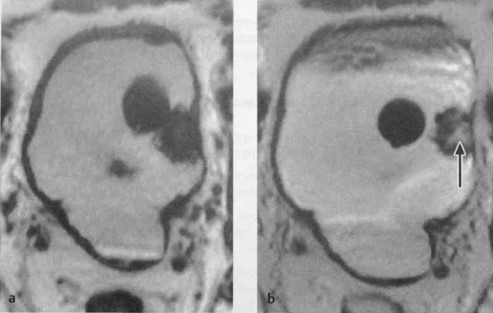

а, b Аксиальная Т1 -взвешенная МРТ: (а) Полиповидное образование, исходящее из левой стенки (катетер Фолея рядом с опухолью). Высокая интенсивность сигнала от содержимого мочевого пузыря обусловлена поступлением контрастного вещества; (b) Хорошая визуализация стенки мочевого пузыря и полиповидного образования (стрелка). Центральное усиление опухоли после внутривенного введения неионного контрастного вещества на основе гадолиния.